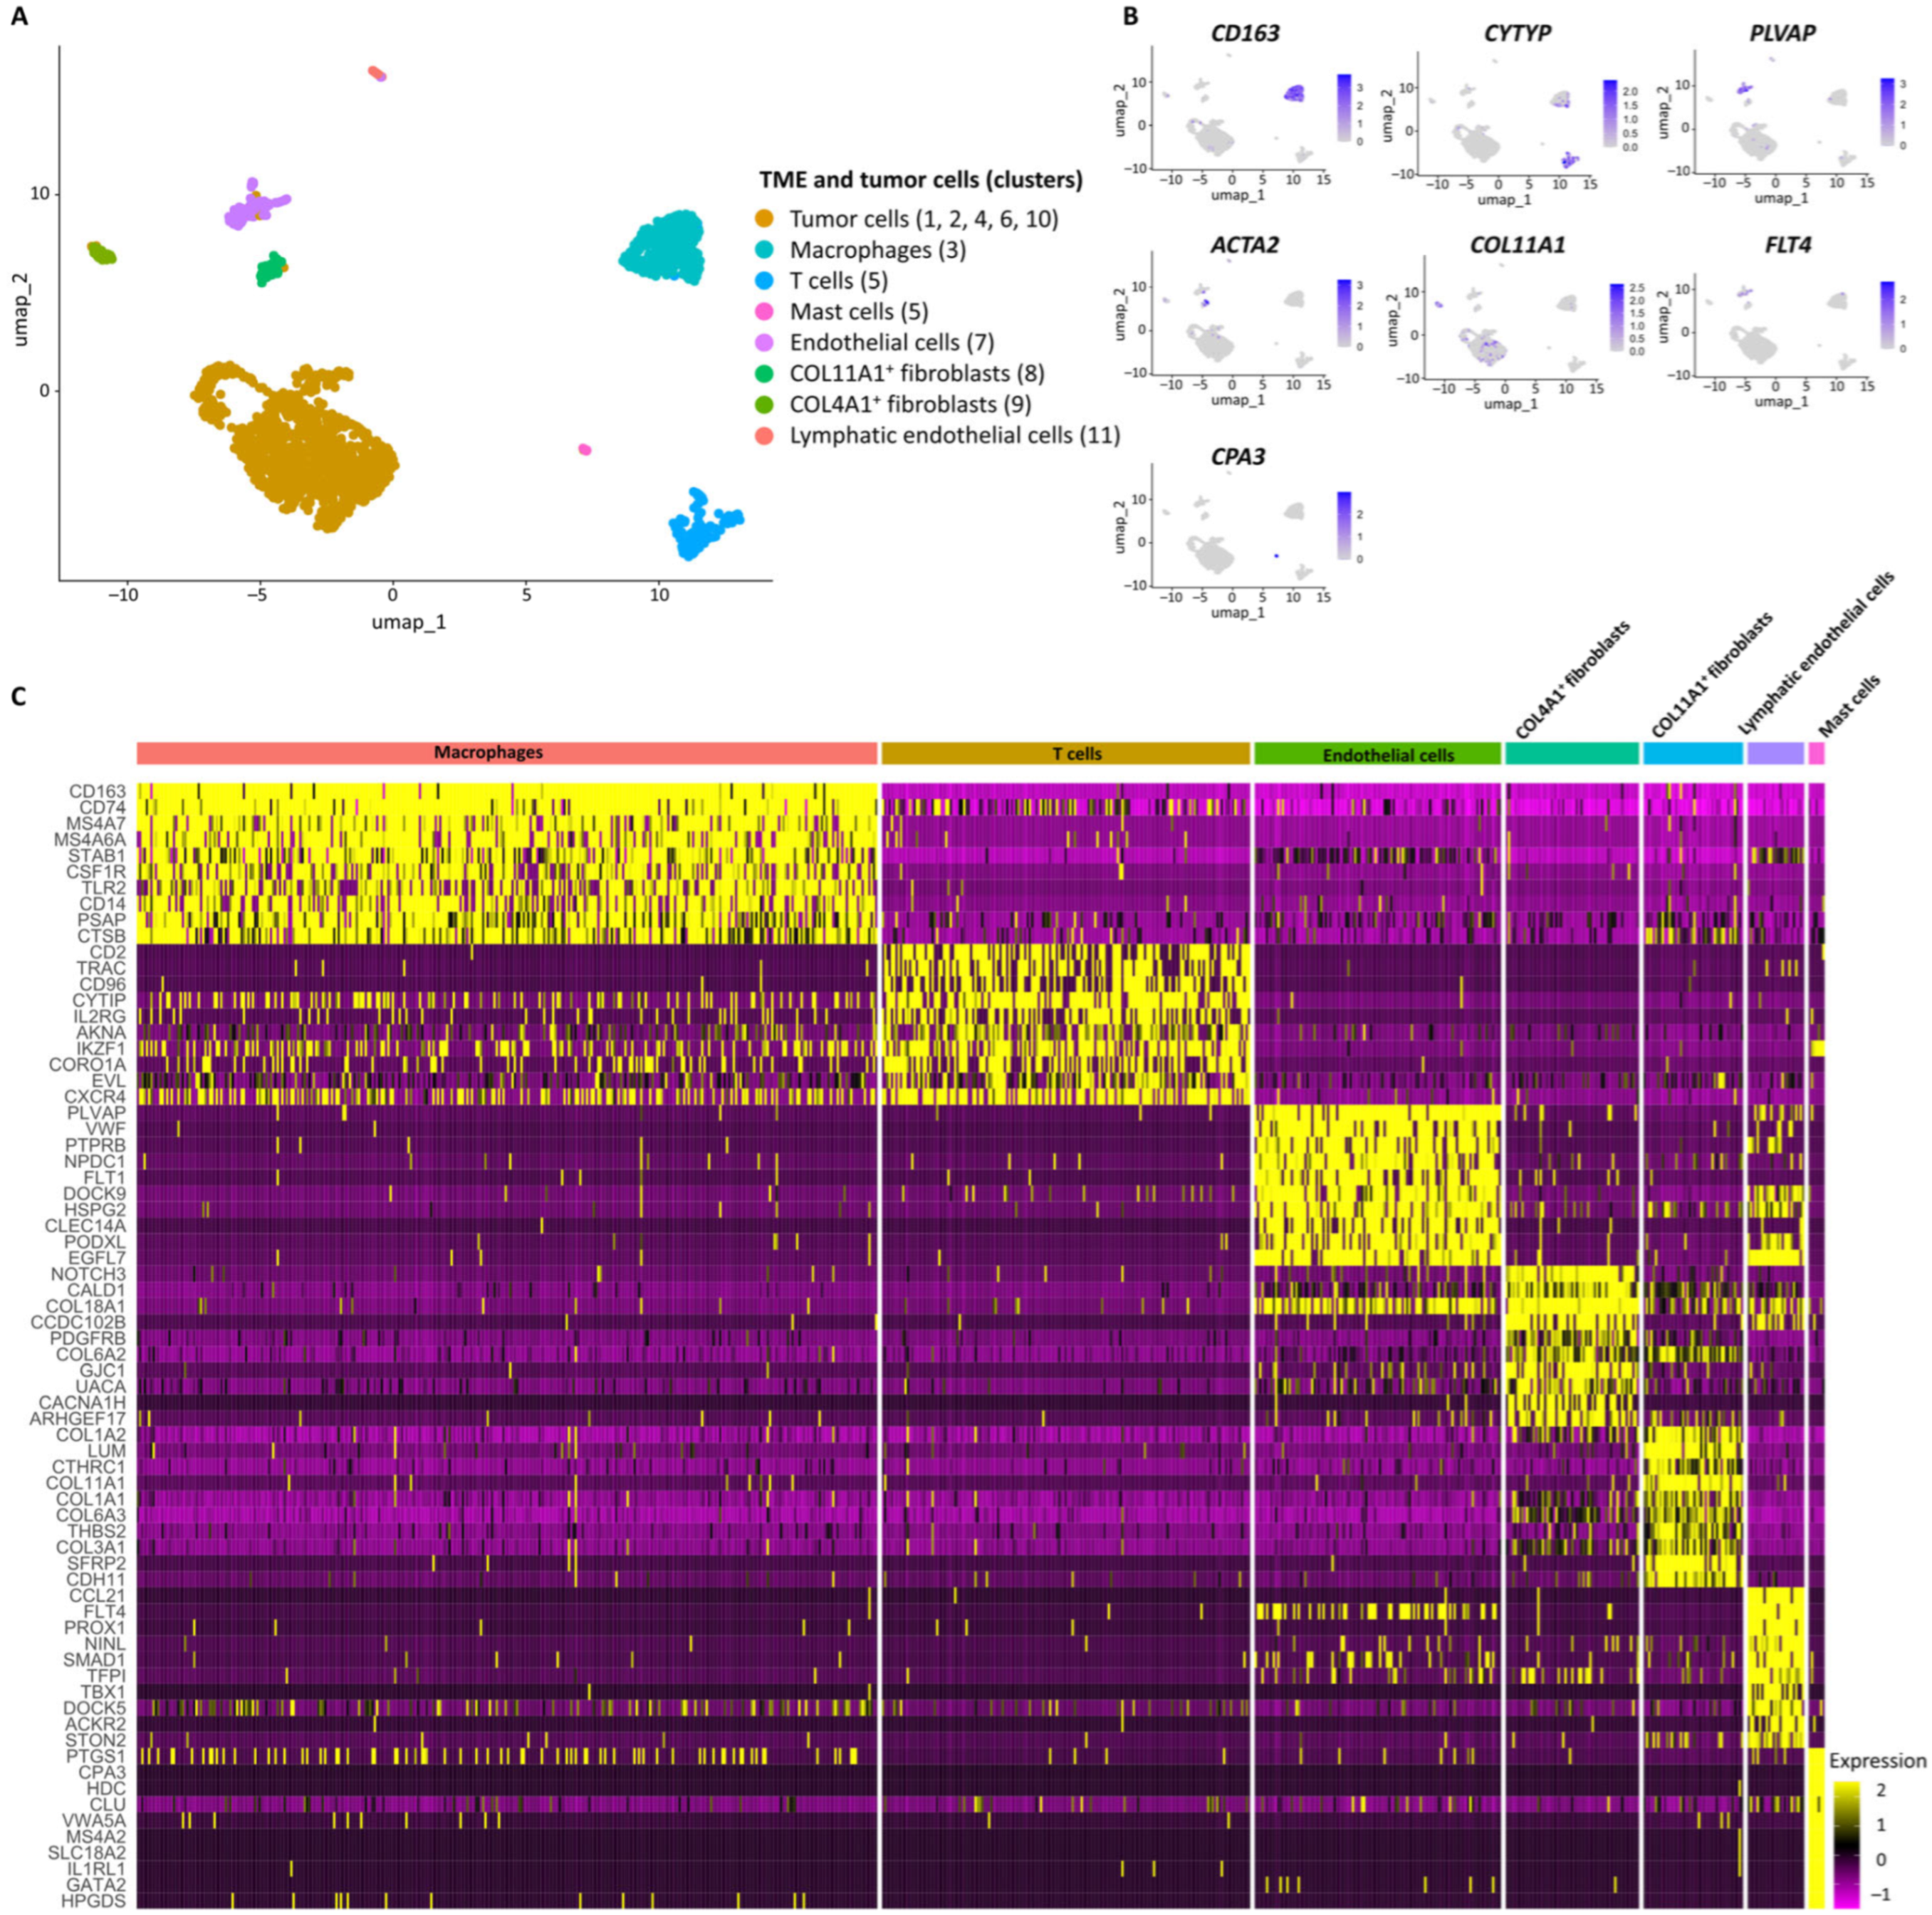

3. Discussion